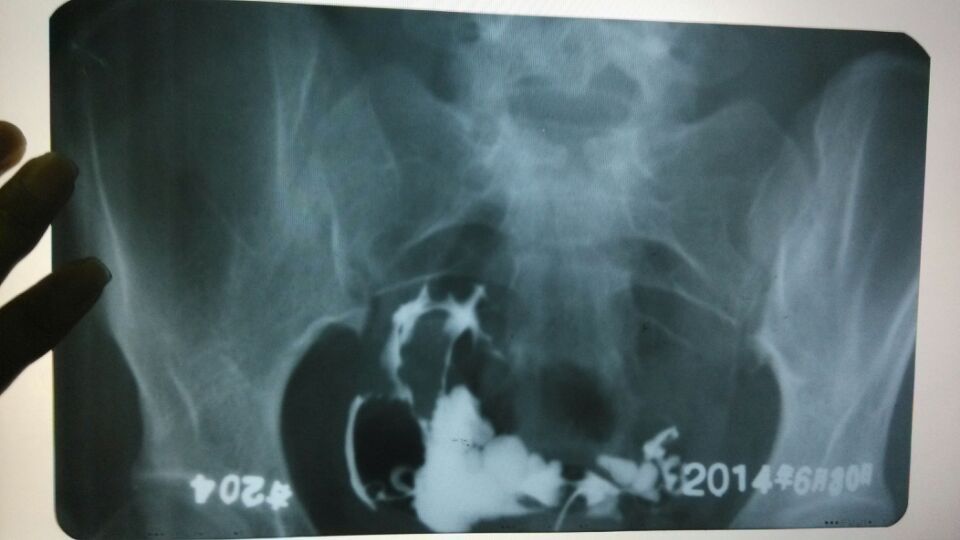

求专家看看输卵管造影拍的片子,昨天做造影的时候很痛

做输卵管疏通要多少钱呢